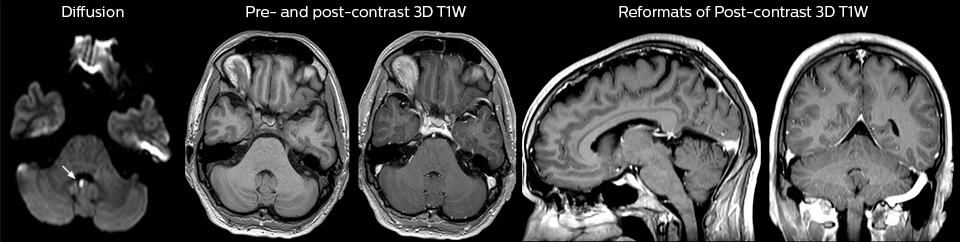

Cervical spine routine exam

This patient presented with headache that was worse with neck flexion and we see a Chiari 1 malformation with low-lying cerebellar tonsils as well as some degenerative cervical thrombolytic change.